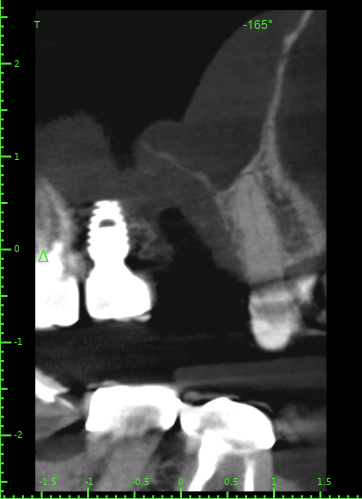

Atcotr Опубликовано 18 июля, 2024 Автор Поделиться Опубликовано 18 июля, 2024 @Женька @red_butler КТ сделано на 17-й день после удаления зуба. Не могли бы вы его посмотреть? Есть ли по вашему мнению свищ или признаки его формирования? Есть ли угроза для 27го импланта? Слизистая в гайморовой пазухе была опухшая задолго до удаления, это не новый процесс. КТ находится по ссылке: https://1drv.ms/f/s!AptB3I-32KWekuk4OkRq7Q6cdU7XcA?e=v69OYx Беспокоит чувство заложенности носа и уха слева после приёма любых жидкостей. Лечащий врач сказал, что небольшие перфорации в 95% случаев зарастают самостоятельно, назначил антибиотик и псевдоэфедрин и следующий приём через месяц. Спасибо за помощь. Ссылка на комментарий

Женька Опубликовано 19 июля, 2024 Поделиться Опубликовано 19 июля, 2024 Материала я, конечно, тут не особо вижу. Возможно он был, но весь вымылся. Перфорация действительно есть. Я бы ждал сейчас заживления и после оценивал формирование сообщения с пазухой. Снимок всю пазуху не вмещает, что там выше возле соустья неизвестно. Ухо, от ситуации на снимке, болеть вряд ли может на мой взгляд. Ссылка на комментарий